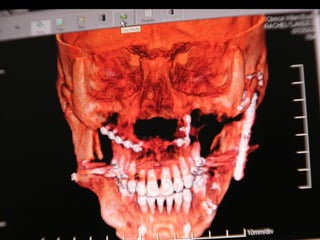

Valoración Clínica dela Paciente En términos generales podemos decir que la paciente tiene una cara armónica y aceptable, sin embargo observaciones métricas delatan: En términos generales podemos decir que la paciente tiene una cara armónica y aceptable, sin embargo observaciones métricas delatan: Laterognatia, manifestada por 3 grados de desviación del Mentón con respecto a la línea media real. Laterognatia, manifestada por 3 grados de desviación del Mentón con respecto a la línea media real. Hipoplasia moderada del maxilar del lado derechoHipoplasia moderada del maxilar del lado derecho Perfil cóncavoPerfil cóncavo Ligera incompatibilidad labialLigera incompatibilidad labial Depresión malarDepresión malar

La paciente muestrauna franca disgnatia, clínicamente observamos malposición dentaria secundaria a la falta de armonía máxilomandibular. La paciente muestra una franca disgnatia, clínicamente observamos malposición dentaria secundaria a la falta de armonía máxilomandibular.

Marcada Clase III HábitoLingual Marcada Clase III Hábito Lingual Sobremordida horizontal: –1.5 mm Sobremordida vertical: + 1 mm. Sobremordida horizontal: –1.5 mm Sobremordida vertical: + 1 mm.